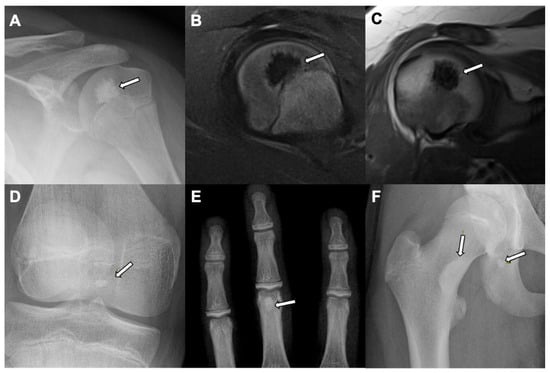

4. Enostosis (Bone Island)

| Lesion Location | Paranasal sinuses, mainly frontal and ethmoidal | Axial skeleton (spine, pelvis, and ribs); long bones | Long bones, mainly femur | Spine and long bones |

| Radiographic/CT features | Juxtacortical, well-circumscribed homogenous sclerotic lesion | Homogenous intra-medullary sclerotic focus with spiculated margins | Small (less than 2 cm) cortical lucency with extensive surrounding sclerosis | Expansile large (more than 2 cm) lucent lesion with matrix mineralization |